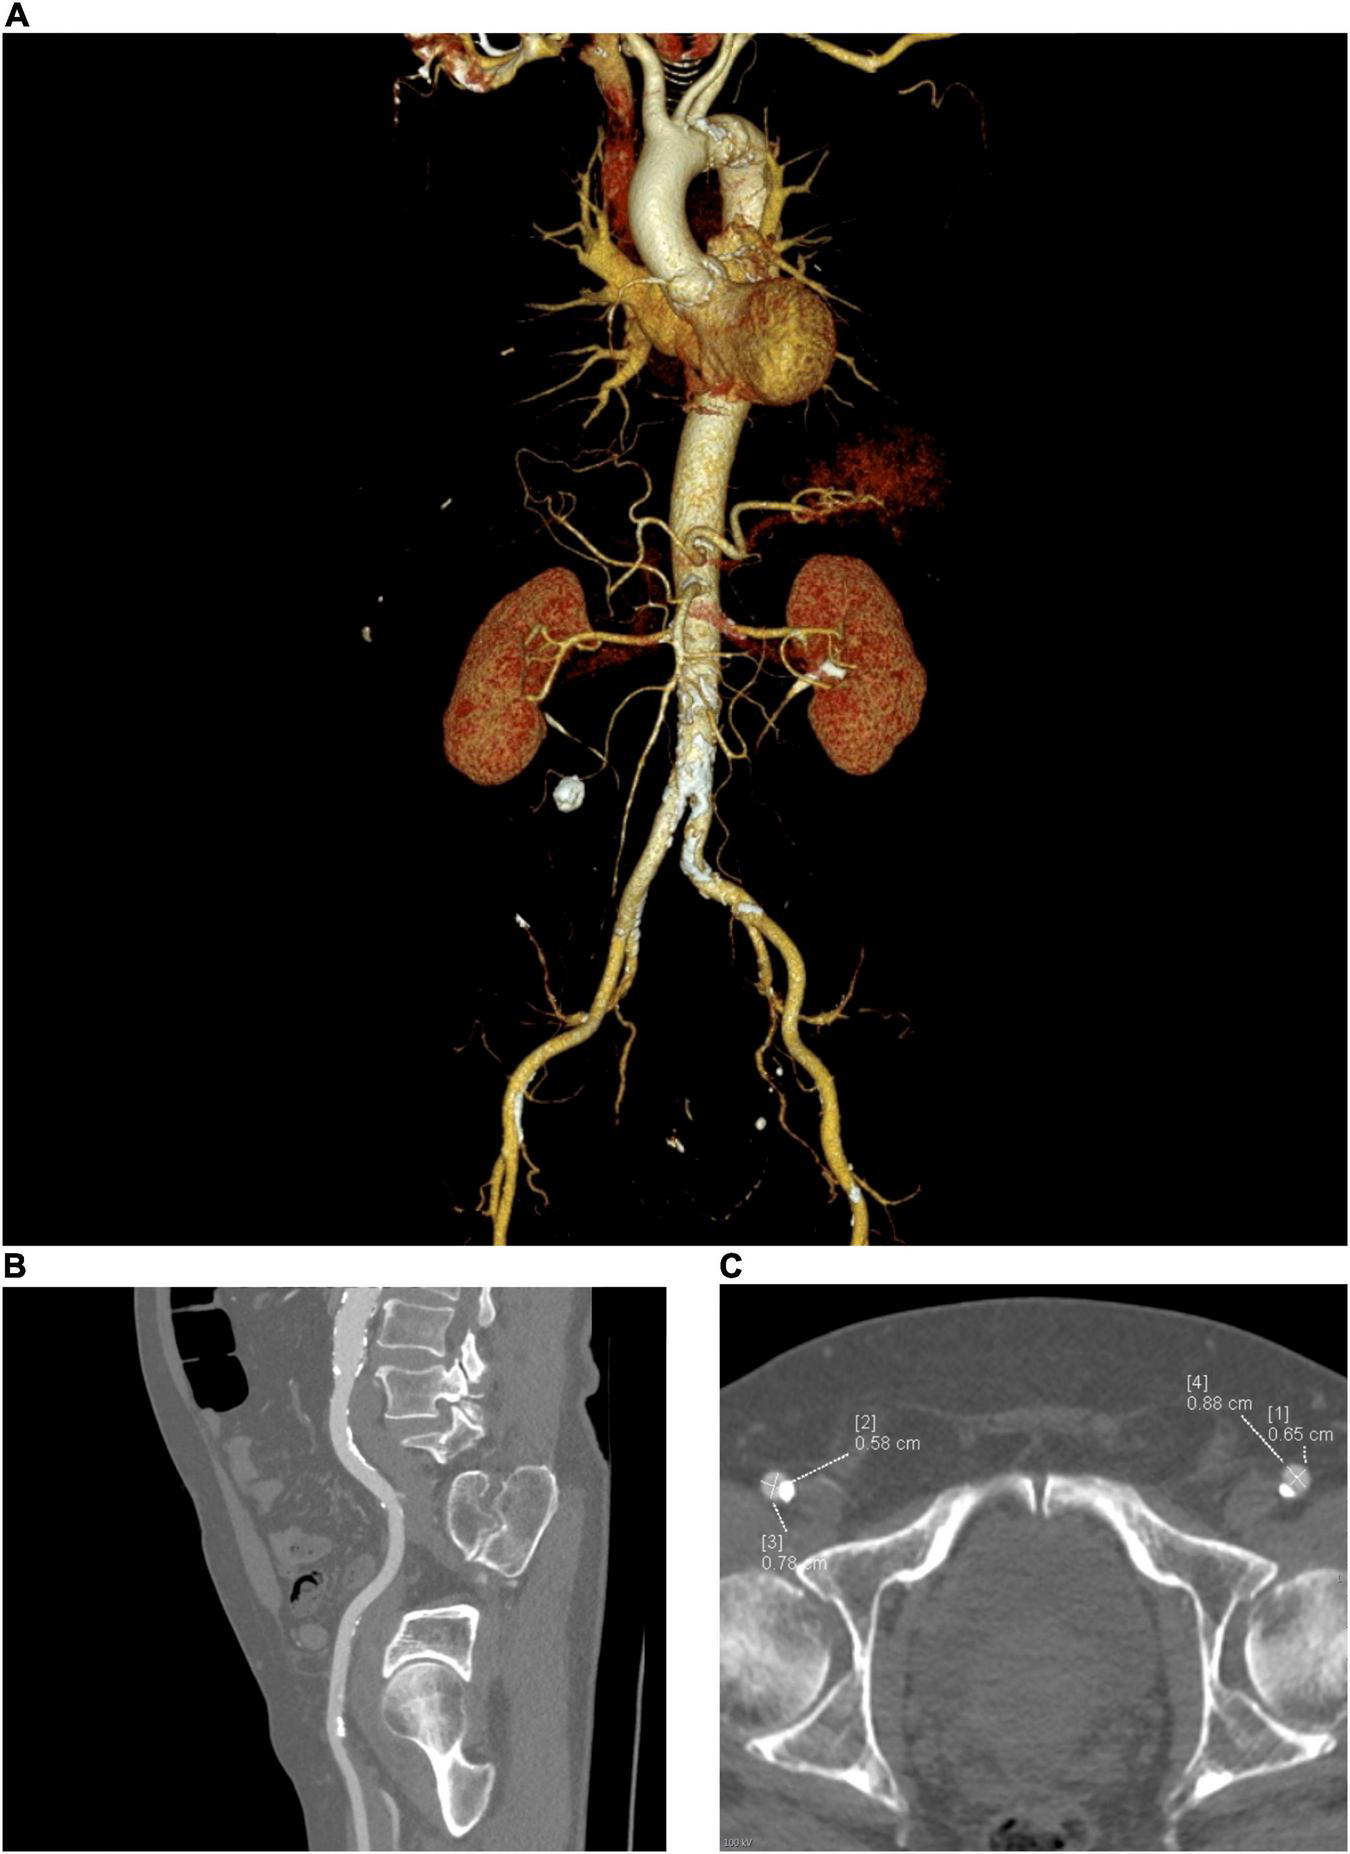

Cardiac computed tomography angiography of the aorta and peripheral vasculature provides a quick and complete dataset for TAVR planning (Figure 1). In addition to illustrating the dimensions of the aortic annulus and root, and degree and distribution of aortic valve calcification, CT can demonstrate the degree of iliac vessel wall calcification, tortuosity, ilio-femoral stenosis, presence of aorto-iliac aneurysms, foci of dissection, large penetrating ulcers, and potentially thrombi, as well as previous vascular procedures with grafting/stent implantation—useful considerations for procedural planning (27–29). When a transfemoral access site is unfavorable, CT can provide valuable information regarding alternative sites, such as subclavian, carotid, apical, trans-aortic, and trans-caval (crossing from the inferior vena cava into the abdominal aorta and using a closure device to plug the aortic wall after implantation of the valve) (30). Trans-caval access is increasingly being used and greatly benefits from pre-procedural planning using CT. Using electrocautery, a puncture is made from the inferior vena cava (IVC) to the adjacent descending aorta between the aortic bifurcation and renal arteries. A calcium-free window on the aorta adjacent to the IVC needs to be located using CT and defined by the vertebral level. Additional measurements such as the distance between aorta and IVC, lumen diameters and identification of bail-out access (in case endograft therapy is required) are useful and can be performed using CT (31, 32).

FIGURE 1

Peripheral access planning for TAVR, requires assessment of the size, tortuosity, calcification (both severity and distribution) and any prosthetic material such as stents or pathologies such as aneurysms. (A) Multiplanar reconstruction of the vascular tree, (B) Sagittal view, (C) Axial view.